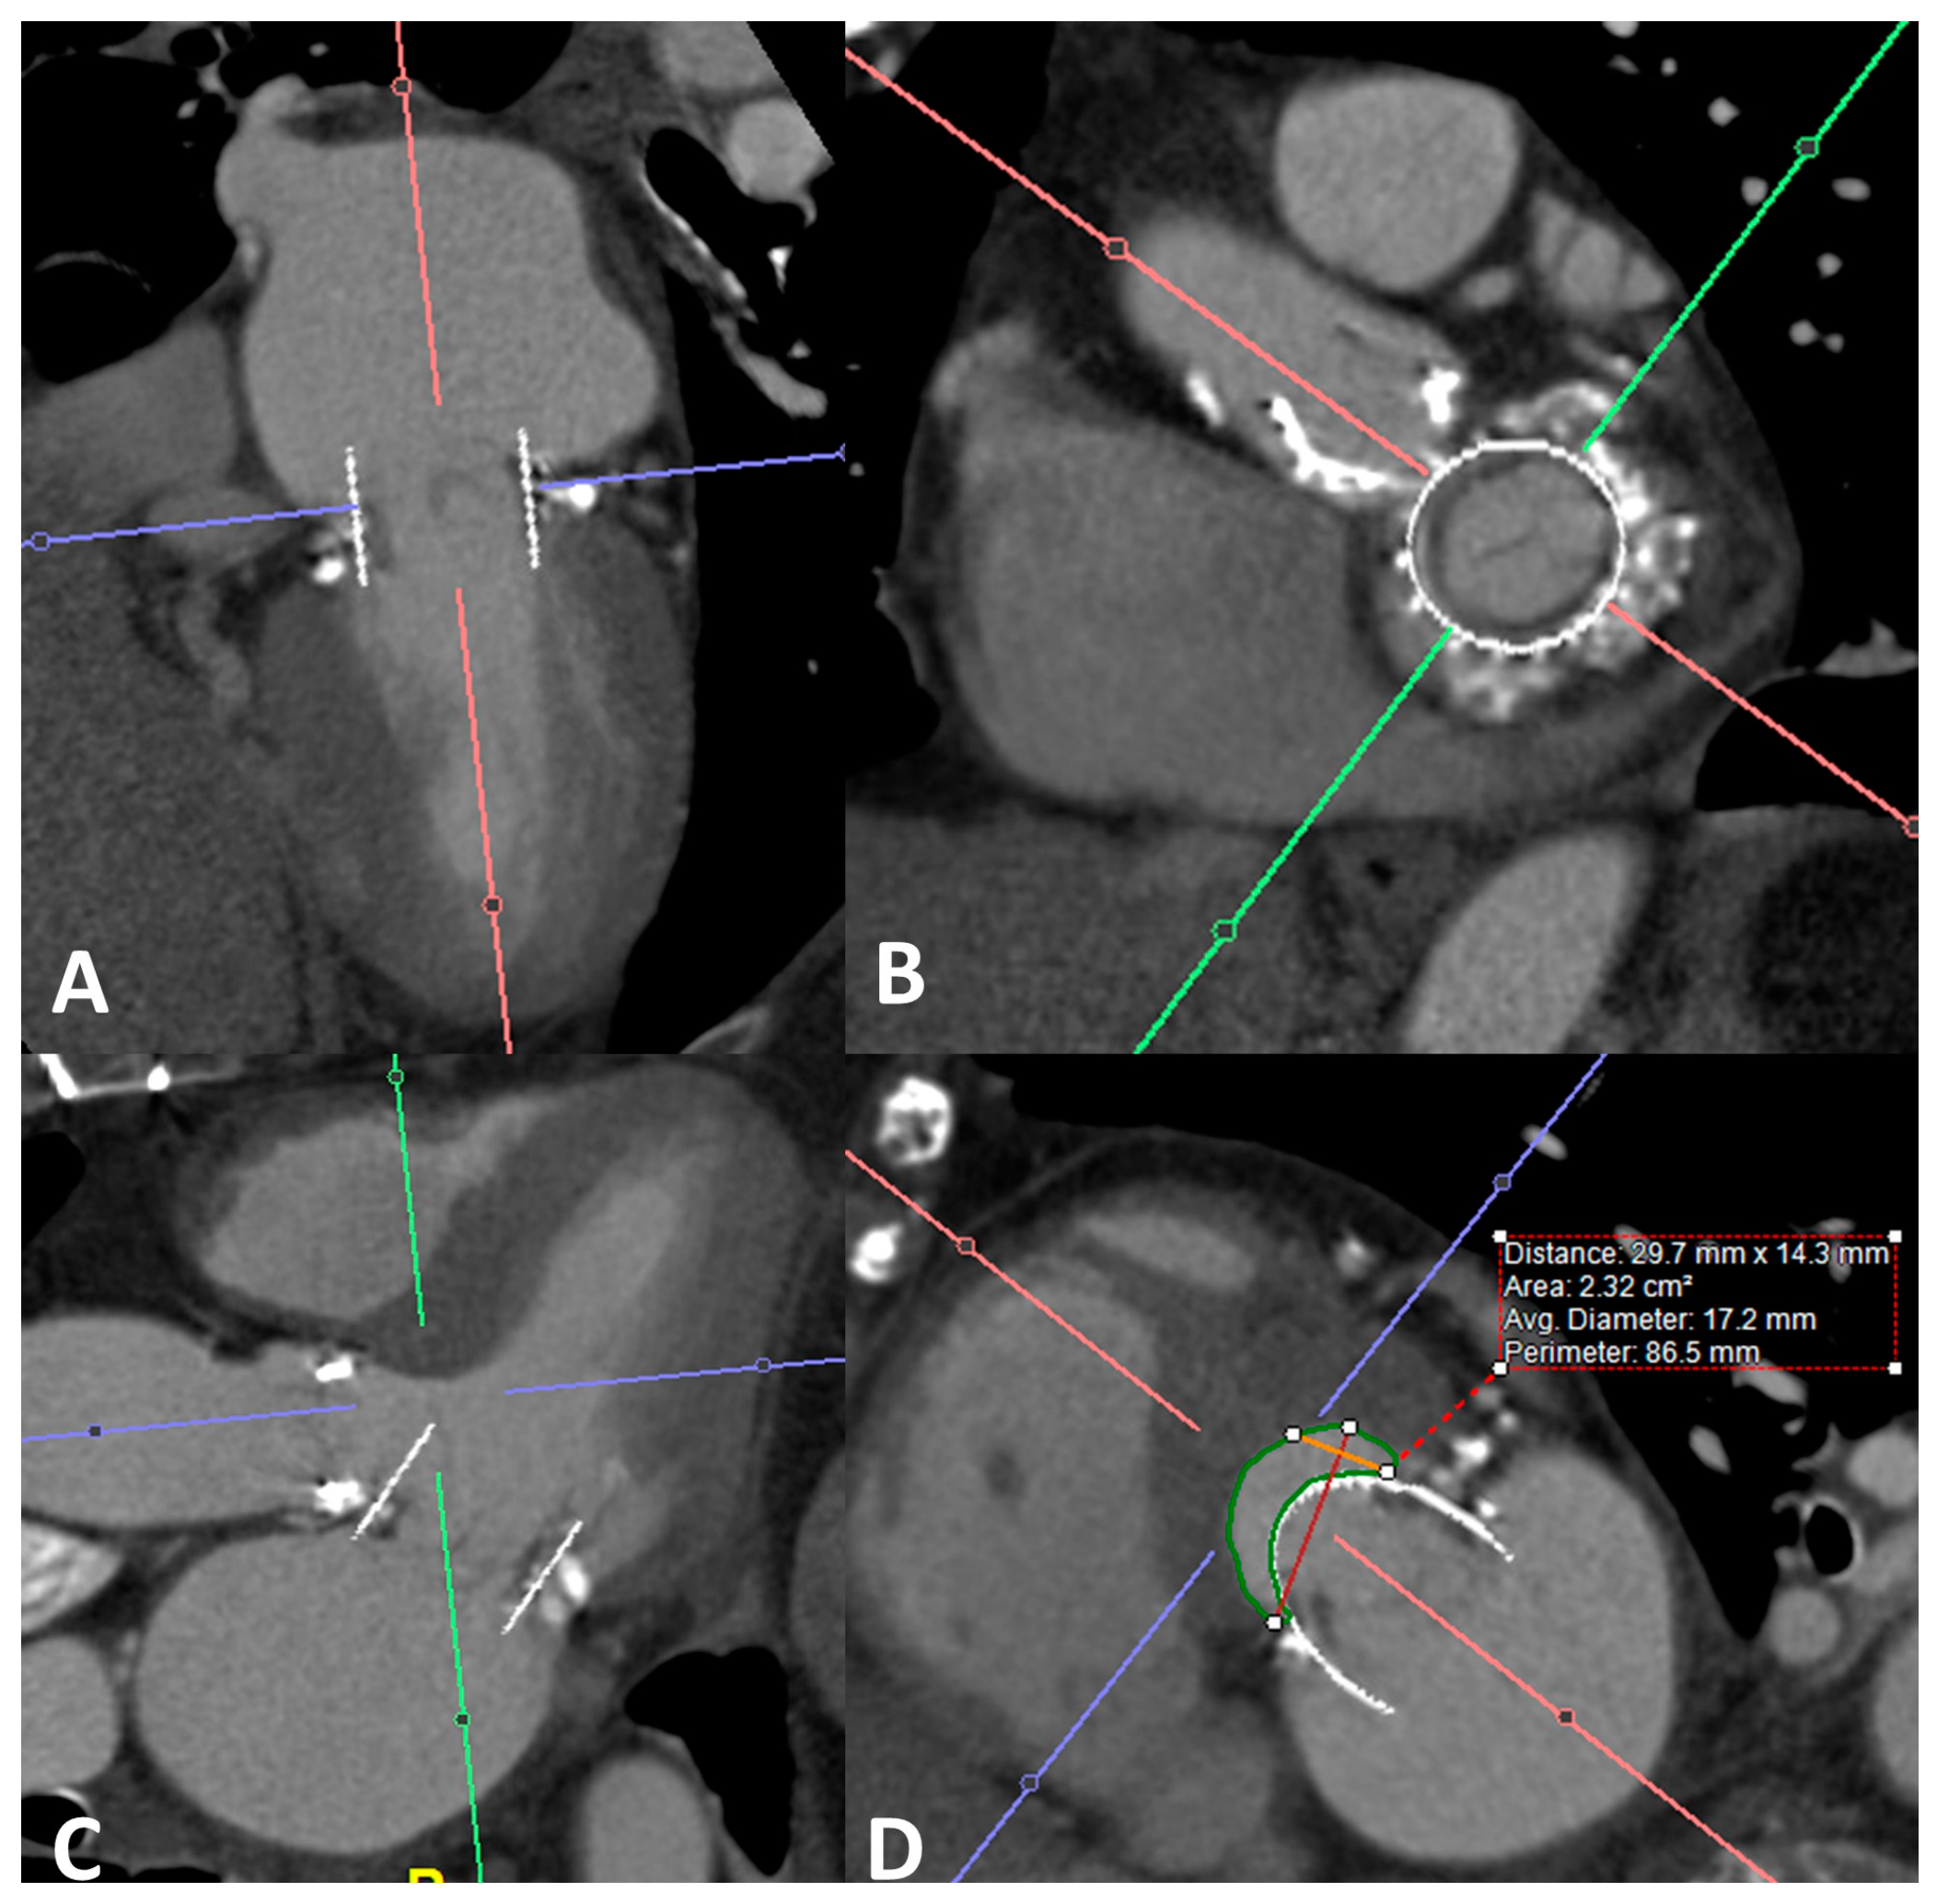

4.3. Valve in MAC

4.4. Differences in Outcomes of Valve in Valve vs. Valve in Ring vs. Valve in MAC